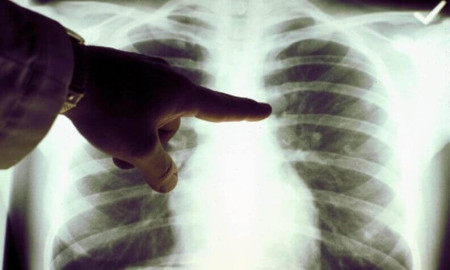

У центральному парку Луцька безкоштовно обстежуватимуть легені

У Луцьку в центральному парку культури та відпочинку імені Лесі Українки всі охочі зможуть безкоштовно обстежити легені цифровим флюрографом.

Захід відбудеться 18 та 19 вересня 2020 року з 12:00 до 17:00 за участі провідного лікаря-рентгенолога.